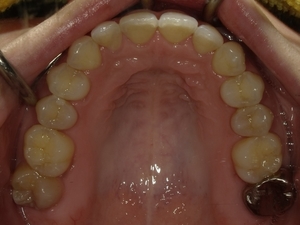

ガタガタとした歯並びや八重歯(叢生)CASE66